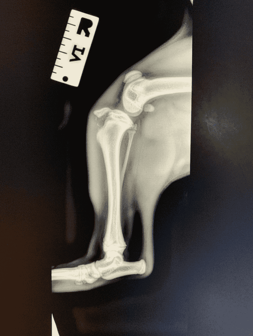

Images (X-rays) is Fred.

A young French Bulldog puppy named Fred presented to our clinic with a history of sudden right hindlimb lameness (limping). The owners didn’t see any major trauma, but they think he might have tried to jump up onto the bed and missed.

When examining the puppy, his right stifle (knee) was painful and swollen. The next steps included x-rays to investigate the limping.

To perform X-rays, we sedated Fred to allow us to (a) obtain good quality X-rays and (b) ensure we (veterinarians & nurses) are not unnecessarily exposed to radiation. Different clinics will use different combinations of medications and dosages for sedations – in this case; we used Medetomidine and Butorphanol. Becoming comfortable with different medication names and their purposes is extremely helpful!

We performed x-rays which revealed the puppy had fractured his tibia (bone in the leg). The specific fracture area was the tibial crest, which is prone to fracturing in young dogs if they hurt their stifle. See the x-rays attached, right and left stifle, for comparison.